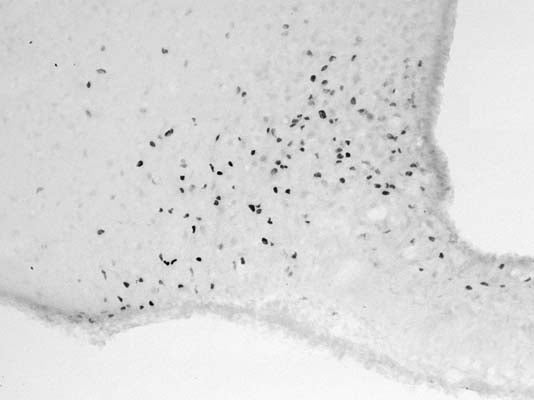

c-Fos was induced in the hypothalamic arcuate nucleus of an adult male Wistar rat with i.p. injection of N-methyl-D-aspartate. The brain was fixed by transcardiac perfusion of the rat with formaldehyde (4%). cFos immunoreactivity was detected on floated cryo-sections of the hypothalamic arcuate nucleus with the S-045-50 primary antibody (1:5000) using the biotinylated secondary antibody-ABC method and nickel-diaminobenzidine chromogen. Photo courtesy of Dr. Erik Hrabovszky, Hungarian Academy of Sciences, Budapest, Hungary.

Click on image to zoom